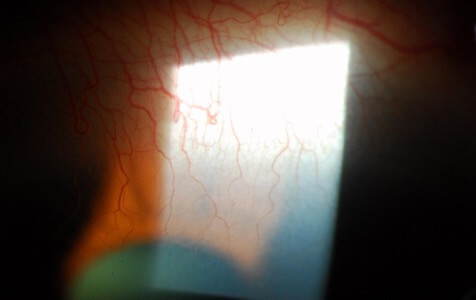

血管擴張

照片由香港理工大學眼科視光學院提供

角膜血管增生

照片由香港理工大學眼科視光學院提供